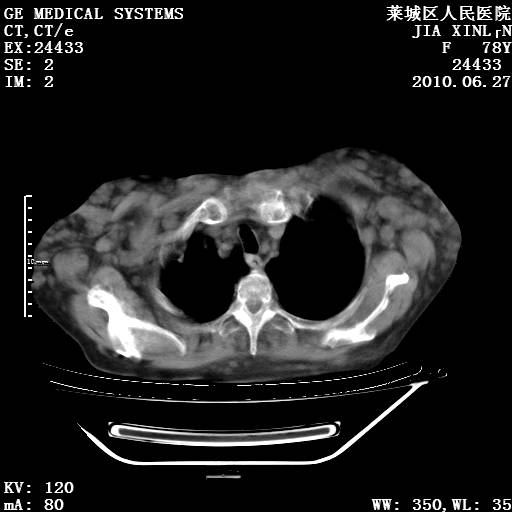

以下是引用胡宇在2010-7-2 19:11:00的发言:[br]神经纤维瘤的特点为:肿块呈多发性、数目不定,少的几个,多的可成百上千难以计数。小的如米粒,大的似拳头,甚至可达十数公斤以上。可松弛地悬挂于皮表,皱褶及松弛可致畸形明显。神经纤维瘤沿神经干的走向生长时呈念珠状,或蚯蚓块状形结节。此外神经纤维瘤皮肤可出现咖啡斑,大小不一,形如雀斑小点状,或大片状,分布与神经纤维瘤肿块的分布无关。肿瘤数目不多的患者,皮肤色素咖啡斑状沉着是纤维神经瘤的重要诊断之一。 本病多发于躯干,有时出现于四肢及面部,患者常合并许多疾病应予重视加以区别。 [br] [br] [br] [br]lyb999说 [br]